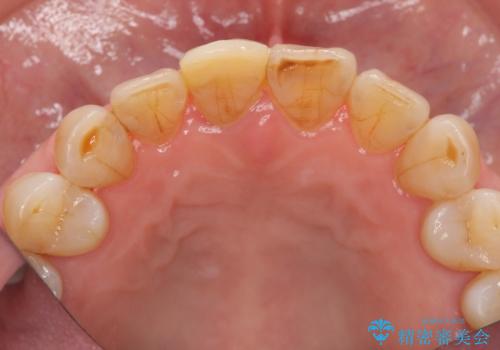

- 前歯を転倒で受傷し、審美性の回復を求めて来院されました。

近医で暫間的なコンポジットレジン修復が為されていましたが、色調に不満があるということでした。

色調の変化が少なく、長期的な予後を見込めるジルコニアクラウンで天然歯を模した審美性の回復を計画します。